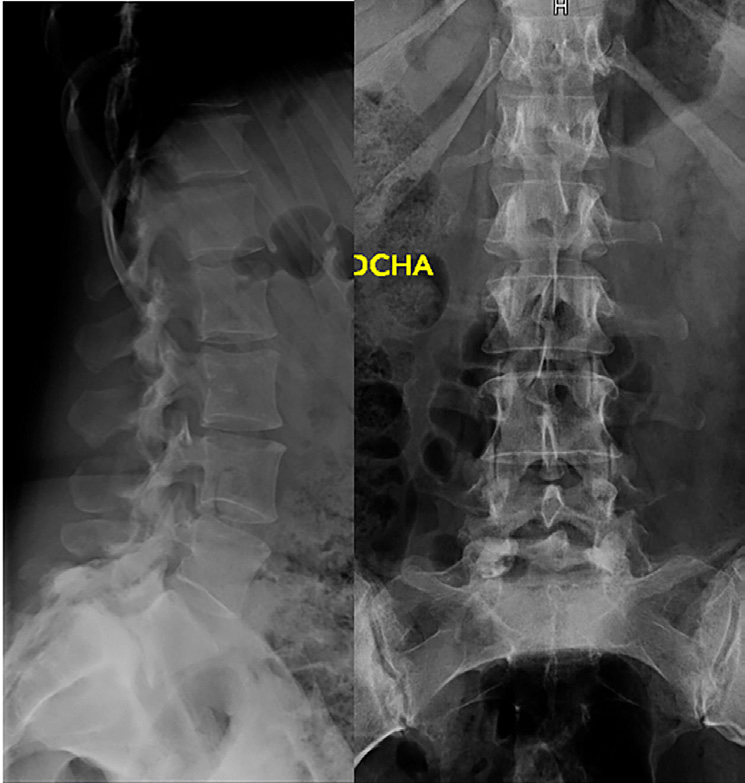

- RMN de columna lumbar: espondilolisis bilateral L5 con espondilolistesis grado II sobre S1. La listesis condiciona discreta estenosis de canal a nivel sacro.

- Radiografías simples columna lumbosacra: espondilolistesis L5-S1 grado II-III.